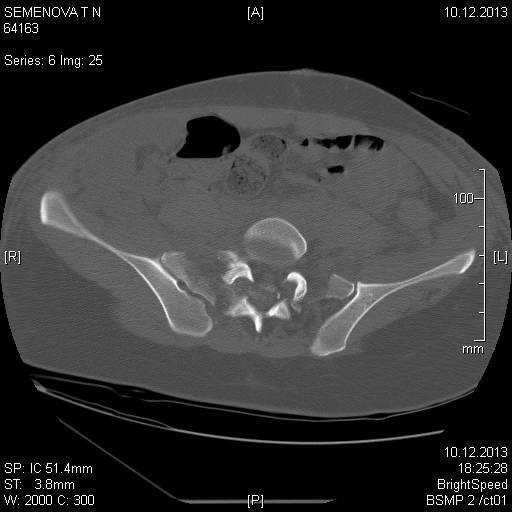

Доброго времени суток коллеги! Прошу вас подсказать тактику в решении оперативного лечения следующего сложного повреждения таза. Был ли опыт в фиксации подобных повреждений? Травма 03.12.2013,больная переведена из лечебного учреждения соседней области.На данный момент у больной следующий диагноз: ЗЧМТ,сотрясение головного мозга;Закр. травма грудной клетки,множественные переломы ребер справа с повреждением ткани легкого,правосторонний гемопневмоторакс,состояние после торакоцентеза;Закр.травма живота,разрыв селезенки,гемоперионеум, состояние после лапаротомиии спленэктомии;Закр. оскольчатый перелом сред-верх\3 левой бедренной кости, состояние после накостного металлостеосинтеза; Закр.поперечный переломовывих на уровне S1S2, многооскольчатый перелом латеральных масс крестца с обеих сторон,перелом обеих лонных и седалищных костей. Перелом поперечных отростков L1,L2,L3,L4, L5 позвонка. ШОК 3ст. Вкратце изложил диагноз. В настоящее время состояние больной тяжелое. Первым этапом планируем наложить АНФ (переднюю раму) После стабилизации состояния необходимо будет выполнить фиксацию: . Имеется один вопрос - какие импланты необходимы т.е. в какой комбинации и какая последовательность фиксации?

Добрый день! Станислав! Повреждение таза действительно тяжелое. В данном случае по мимо перелома передних колонн, что не самое страшное, имеется H-образный перелом крестца со смещением каудальной части. перелом поперечных отростков подтверждает вертикально нестабильный характер травмы таза. Предложенная конструкция действительно является вариантом решения проблемы,а скомпоновать ее можно из любого транспедикулярного фиксатора той фирмы которая работает у вас с нейрохирургами.Но помимо этого необходимо выполнить декомпрессию корешков конского хвоста. в противном случае та неврология которая есть и сейчас останется на всю жизнь. Судя по тяжести состояния к лечению перелома крестца сможете приступить не скоро, скорее всего на данный момент доминирует легочный дисстресс синдром, наверняка есть анемия после гемопневмоторакса, лапаротомии и накостного остеосинтеза бедренной кости.Поэтому когда дойдет дело до крестца репонировать отломки будет весьма сложно. Мы бы начали с остеосинтеза ребер, чтобы сделать пациента мобильным, передние колонны можно фиксировать перкутанно винтами, сзади кроме илиолюмбальной конструкции, ляминэктомия с целью декомпрессии, репозиция и дополнительная фиксация реконструктивными пластинами, лучше LCP. Пригласите на операцию нейрохирурга-вертебролога. Успехов.

При переломо-вывихах крестца неврологический статус является одним из основных показаний к оперативному лечению. Наличие неврологических симптомов ускоряет процесс, и проблему надо решить ургентно в первые дни..

В данном случае кроме фиксации крестца требуется декомпрессия канала. А вправленный вывих надо удержать, и вертикальные пластины с юникортикальной возможностью в 2.7 мм помогут создать стабильность. Кроме этого, надо создать условия по предупреждению компрессии крестца с двух сторон. В связи с тем, что процедура заканчивается в области крестца, а также наличие повреждения позвонков, это ограничивает возможности педикулярной фиксации. Мне кажется, от боковой компрессии лучше удержала бы согнутая по контуру крыла узкая в 4.5 мм балка-пластина.